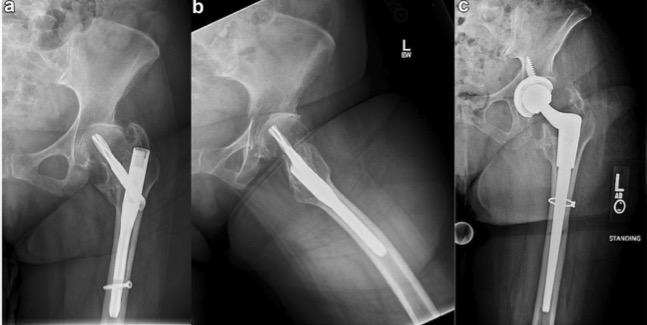

This is one of those papers you save to that folder on your desktop: “Essential technique papers”

@ArthroToday

Arthroplasty Today

2 years

What are your tips for THA after prox femoral nailing? This technique paper has advice on using diff extraction sets, intraop imaging, what to do with a broken nail, &more! @bethgausdenmd @DrPeterSculco @jaimelbellamyDO @Hassan_Mir_MD @lisacannada https://t.co/lA9J7cSlW9